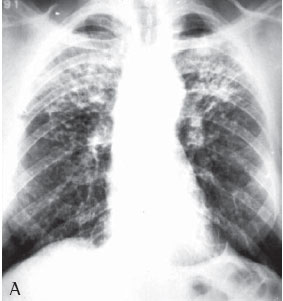

Quanto à classificação radiológica das grandes opacidades na radiografia de tórax verificou-se que: 23 pacientes apresentaram grande opacidade do tipo A (30,7%), 25 do tipo B (33,3%) e 27 do tipo C (36%) (Figuras 1A e 1B). Dos casos analisados, 74 apresentaram massas conglomeradas bilaterais, e apenas 1 apresentou lesão unilateral (Figuras 2A e 2B).

Mais da metade dos pacientes com silicose complicada apresentou na radiografia de tórax grandes opacidades dos tipos B e C, o que denota a gravidade da doença nestes pacientes.

De todos os casos analisados (n = 75), apenas um apresentou grande opacidade unilateral simulando massa tumoral, sendo o diagnóstico de silicose feito através de toracotomia com biópsia pulmonar a céu aberto. Lesões solitárias de FMP são freqüentemente confundidas com câncer de pulmão. Considerando-se a maior incidência de câncer de pulmão nesses pacientes, é importante fazer uma abordagem diagnóstica para efetivamente diferenciar as lesões malignas das lesões benignas pneumoconióticas.(19)